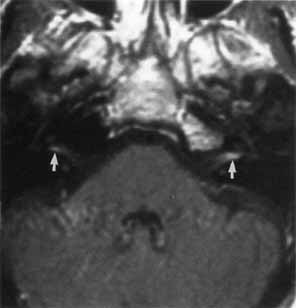

Lyme disease may cause unilateral or bilateral facial paralysis (Fig. 12).53 This disease is characterized by erythema chronicum migrans, tick-borne meningopolyneuritis, myocardial conduction abnormalities, and Lyme arthritis. The disorder was first recognized in 1975 by close geographic clustering of children with arthritis in the small community of Lyme, Connecticut. The spirochete B. burgdorferi is transmitted by an arthropod vector (the deer tick, Ixodes dammini). The skin lesion begins as a red macule or papule and expands to form a large red ring with partial central clearing. The lesion typically lasts about 3 weeks or longer (Fig. 13). Associated symptoms include malaise, fatigue, chills, fever, headache, myalgias, nausea, vomiting, and sore throat. Some patients develop a spectrum of neurologic symptoms and a clinical picture suggesting collagenosis, syphilis, or multiple sclerosis.

Fig. 12 Axial T1-weighted, gadolinium-enhanced MRI showing bilateral proximal facial nerve enhancement (arrows) in patient with Lyme disease and facial diplegia.